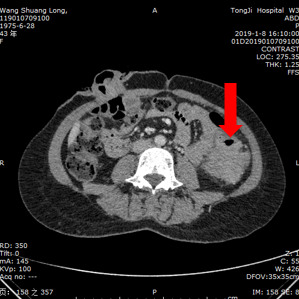

2019.1.8复查CT

结肠病灶较前稍有增大;

盆腔病灶较前明显增大,并出现新发囊性病灶;

总体评价为PD。

影像学资料:

2019.1.8腹部CT